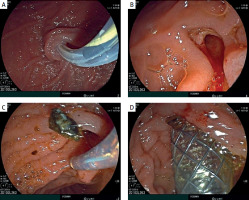

On 13th December 2022: During the endoscopy, the major duodenal papilla (MDP) was not enlarged. The common bile duct (CBD) was catheterized: the proximal part measured up to 1.0 cm in diameter, while the middle and lower thirds were cystically dilated to 2.5–3.0 cm, forming two cavities. Two shadows, measuring 1.1–1.3 cm in diameter, were observed in the lumen of the CBD in the distal part (Figure 3). Endoscopic papillosphincterotomy (EPST) was performed up to 0.7 cm with additional balloon dilation to 1.1 cm. The stones were extracted.

During the procedure, subcutaneous emphysema of the chest, neck, and face was identified, suggesting a possible rupture of the choledochal cyst wall and the entry of air from the abdominal cavity into the mediastinum. To close the rupture of the choledochal cyst, it was decided to place an endobiliary stent. A metallic fully covered endobiliary stent, 6.0 cm in length, was placed in the CBD. After the stent placement, bile began to flow through the stent (Figure 4). After the placement of the endobiliary stent, no further progression of the subcutaneous emphysema was noted.

Figure 4

A – Catheterization of the common bile duct with a papillotome over a guidewire. B – Endoscopic papillosphincterotomy up to 0.7 cm with additional balloon dilation. C – Choledocholithotripsy. D – Insertion of a self-expanding metal stent